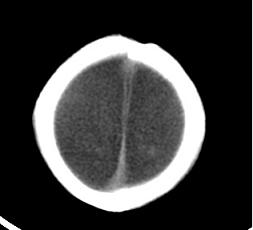

男,4个月大,2个月前无诱因下四肢抽搐、伴呕吐,近2天来抽搐频发,伴发热。查体:双眼疑视,神萎、纳差;颈抵抗,四肢张力高。

病史太长了,原因不好定,不过如果2个月前小儿正常的话可考虑积水型无脑畸形,积水型无脑畸形小儿刚生下来表现可正常,存活一两个月后出现症状.

另不除外缺血缺氧性脑病,感染等改变

2个月前缺血缺氧性脑病留下的后遗症。

脑出血后,软化灶形成了。脑发育不良

支持缺血缺氧性脑病留下的后遗改变(脑软化灶+脑发育不全+双侧慢性硬膜下积液+小头畸形)。

要注意化脓性脑膜、脑炎,硬膜下积脓,脑积水的可能,建议腰穿助诊。